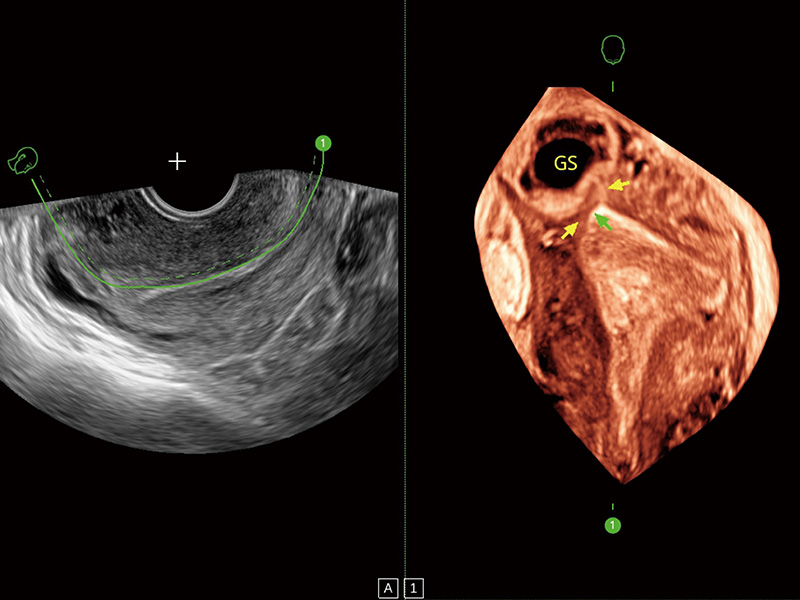

“生育问题”即关系民族复兴,也关系亿万家庭的幸福。随着婚育年龄推迟、社会压力增加等因素,越来越多人群也面临着“生不出、生不好”的问题。辅助生殖作为治疗不孕不育最有效的方法之一,也逐渐成为育儿新希望。而超声检查能为生殖需求人群的初诊评估提供宝贵的信息。 P20 Elite是狗万官方网站匠心打造的一款生殖应用型彩超。她继承狗万官方网站高端极光平台,突破性地将多款新型芯片及硬件模块进行整合,均衡了高端系统性能与小巧灵动机身。P20 Elite卓越的图像质量搭载专科探头,旨在为您提供全面的辅助生殖解决方案。

P20 Elite配备了丰富的生殖探头群和临床应用功能,在卵泡监测、穿刺取卵、胚胎移植、妊娠确认等领域,为生殖需求人群提供了新的临床机会,重新定义高端超声如何应用于生殖健康检查。